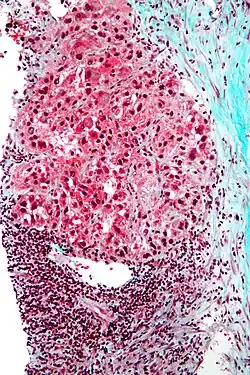

Macroscopically, liver cancer appears as a nodular or infiltrative tumor. The nodular type may be solitary (large mass) or multiple (when developed as a complication of cirrhosis). Tumor nodules are round to oval, gray or green (if the tumor produces bile), well circumscribed but not encapsulated. The diffuse type is poorly circumscribed and infiltrates the portal veins, or the hepatic veins (rarely).[20]

Microscopically, the four architectural and cytological types (patterns) of hepatocellular carcinoma are: fibrolamellar, pseudoglandular (adenoid), pleomorphic (giant cell), and clear cell. In well-differentiated forms, tumor cells resemble hepatocytes, form trabeculae, cords, and nests, and may contain bile pigment in the cytoplasm. In poorly differentiated forms, malignant epithelial cells are discohesive, pleomorphic, anaplastic, and giant. The tumor has a scant stroma and central necrosis because of the poor vascularization.[46] A fifth form – lymphoepithelioma like hepatocellular carcinoma – has also been described.[47][48]